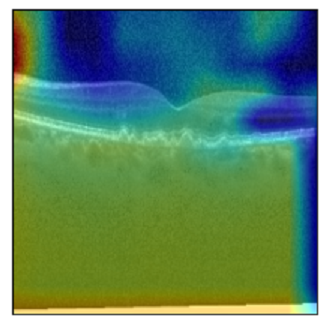

Original Image

Explanation B

Explanation C

Explanation D

GradCAM

Original Image

Explanation B

Explanation C

Explanation D

GradCAM

V MODEL EXPLANATION WITH XAI

Fig 6, 7, 8 and 9 depicts the visualization of correct predictions by our proposed CNN model where fig 6 is class CNV, fig 8 is class DME, fig 7 is DRUSEN and finally, fig 9 is NORMAL. Here the first photo in every class is the original image. The LIME map of our suggested model’s prediction is shown in image B whereas in image C the positive region is highlighted in specific sections on the original image. For Image D we have increased the number of features from 5 to 10 thus more regions have been predicted as the positive region which is highlighted in green. After increasing the features from 5 to 10, some of the regions are predicted wrongly. The red regions represent the output of incorrect prediction. The following image represents the Grad-CAM heatmap highlighting the regions with our model’s prediction.